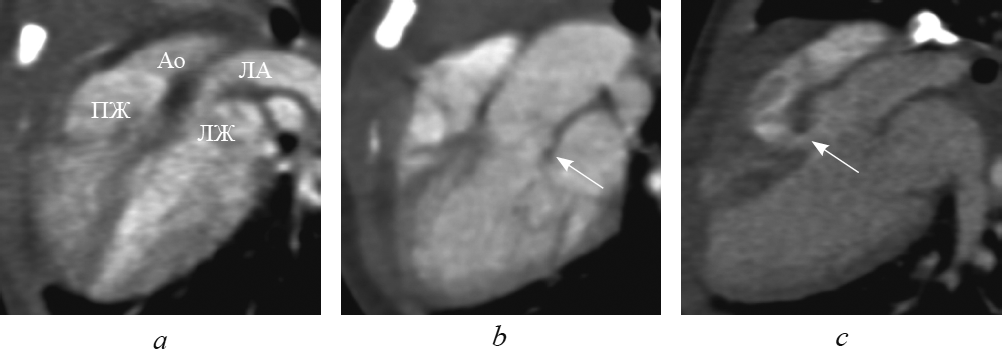

Рис. 7. В реформации по длинной оси левого желудочка при транспозиции магистральных сосудов: выходные тракты и магистральные артерии расположены параллельно (а); определяются митральное полулунное фиброзное продолжение (b, стрелка) и дефект межжелудочковой перегородки (c, стрелка). Ао — аорта; ЛА — легочная артерия; ЛЖ — левый желудочек; ПЖ — правый желудочек

Fig. 7. Long-axis of left ventricle reformation in great arteries transposition: outflow tracts and great arteries are parallel (а); semi-lunar fibrous prolongation (b, arrow) and interventricular sept defect (c, arrow) are determined. Ао – aorta; ЛА – pulmonary artery; ЛЖ – left ventricle; ПЖ – right ventricle

Достоверно визуализировать митрально-полулунное фиброзное продолжение, представляющее собой фиброзный контакт легочного клапана с митральным клапаном, при транспозиции удалось в 10 случаях (рис. 7, b). Дефект межжелудочковой перегородки визуализировался во всех случаях (рис. 7, c). В реформации по длинной оси левого желудочка удалось определить стеноз выходного тракта левого желудочка (рис. 8).

При транспозиции в этой реформации, в отличие от нормы, выходные тракты и магистральные артерии расположены параллельно. При этом визуализируются два параллельно расположенных сосуда: аорта — спереди от легочной артерии, которая является продолжением правого желудочка; легочная артерия — кзади от аорты, которая является продолжением левого желудочка (рис. 7, а). Параллельный ход магистральных артерий четко визуализируется и в реформации приточных отделов желудочков.

При корригированной транспозиции в этой реформации выходные тракты и магистральные артерии расположены параллельно. При этом визуализируются параллельно расположенные желудочки с отходящими от них магистральными сосудами: аорта — спереди от легочной артерии, которая служит продолжением морфологически левого желудочка; легочная артерия — кзади от аорты, которая служит продолжением морфологически правого желудочка.